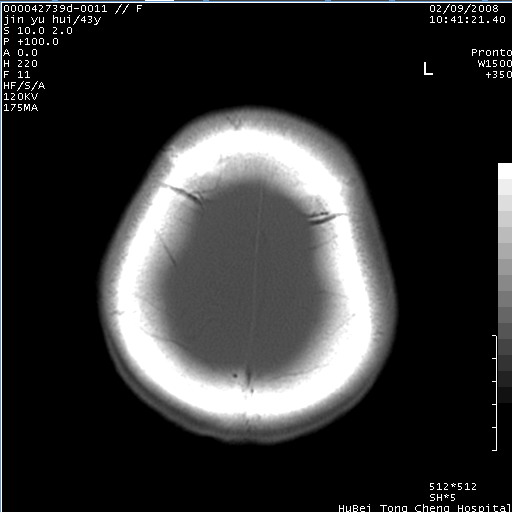

患者 女,43岁。头部外伤26天,经住院治疗,现头痛减轻。申请ct复查,了解颅内情况。

临床诊断:2级脑外伤。

颅脑ct轴位平扫(层厚、层距均为10mm),图像如下:

纵裂旁硬膜下水瘤,左额部头皮肿胀

大脑镰左旁慢性硬膜下血肿.左额部头皮血肿.